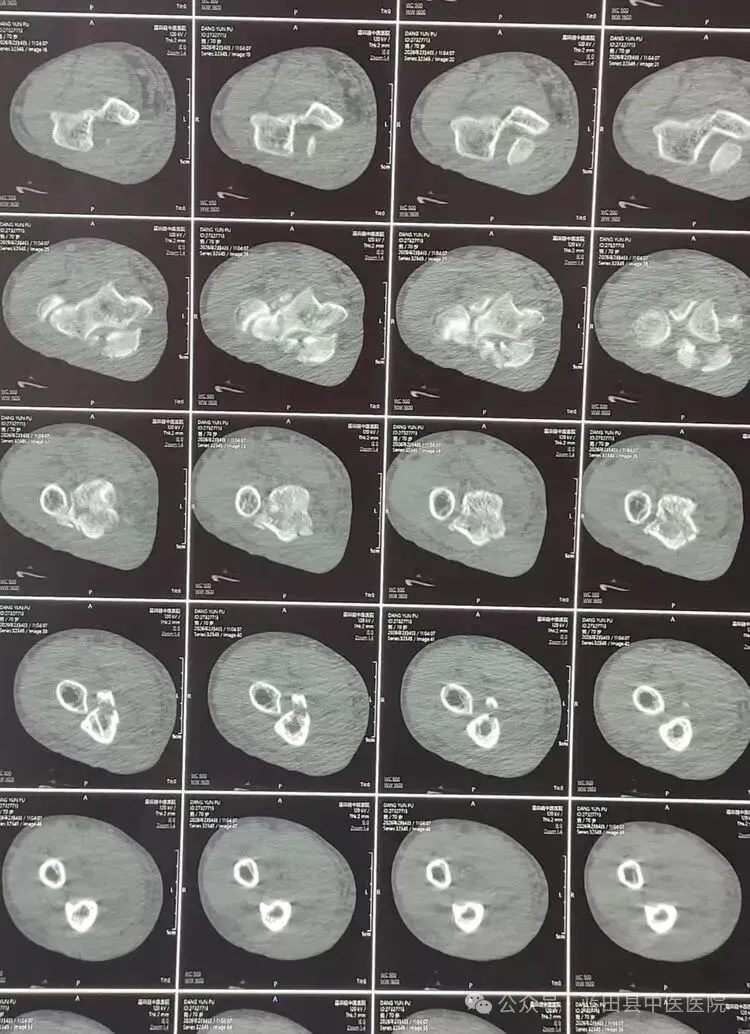

70岁的党某某老人意外遭遇尺骨鹰嘴骨折,右肘关节肿胀明显,周围浮现淤斑,关节活动严重受限,剧烈的疼痛让老人饱受困扰。紧急就医后,X线摄影成像清晰确诊病情,为后续治疗提供了关键依据。

接诊后,蓝田县中医医院谢锋勃副主任医师高度重视,结合老人的年龄、骨折程度及身体状况,细致完善各项检查,全面评估手术风险与康复潜力。为确保治疗方案的科学性与安全性,谢锋勃与支军龙两位副主任医师共同研讨,优化手术细节,采用尺骨鹰嘴切开复位内固定术,力求以精准操作实现骨折端的完美复位,为后续康复奠定坚实基础。